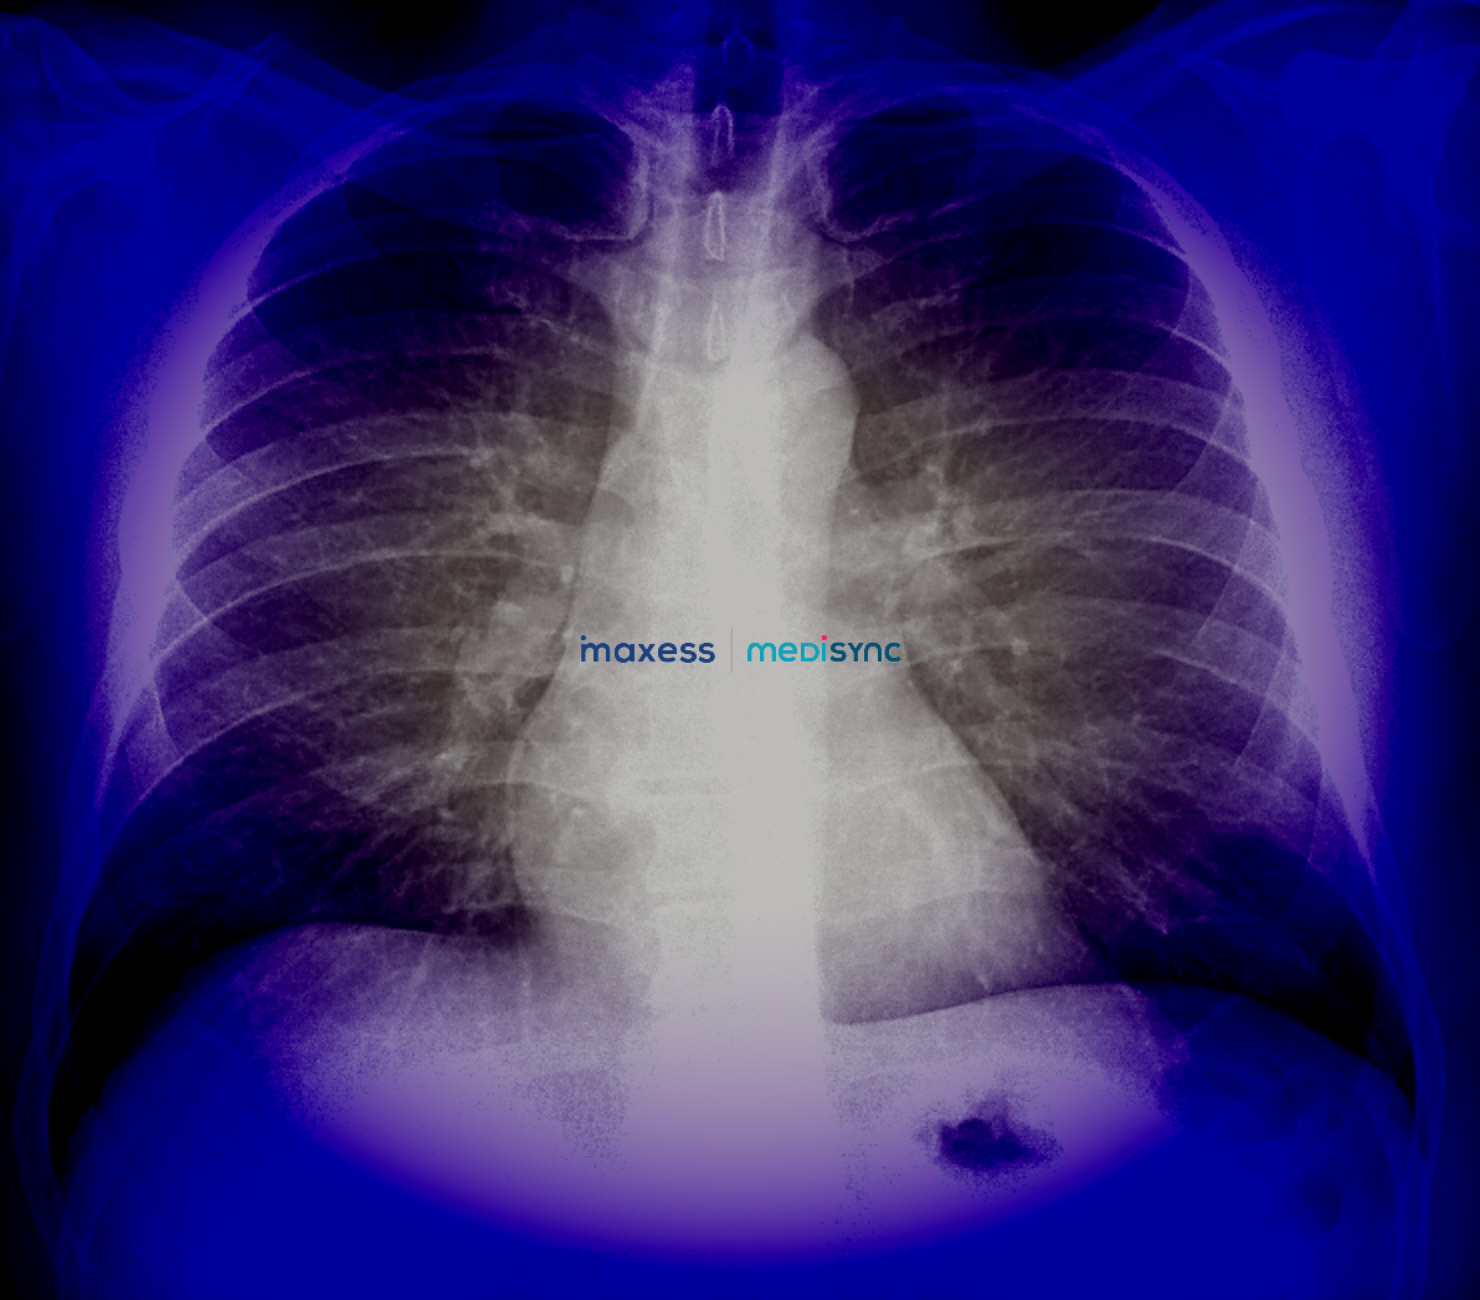

- Propósito: Los Rx se utilizan para diagnosticar o evaluar una amplia gama de condiciones médicas, como fracturas óseas, infecciones, cáncer, neumonía, obstrucciones intestinales, enfermedades cardíacas y dentales, entre otras.

- Proceso: Durante un Rx, se coloca al paciente frente a una máquina de rayos X y se le pide que se mantenga quieto mientras se toma la imagen. El técnico de radiología posiciona al paciente y puede utilizar dispositivos como placas de rayos X o detectores digitales para capturar las imágenes. El paciente puede tener que adoptar diferentes posiciones según la parte del cuerpo que se esté examinando.